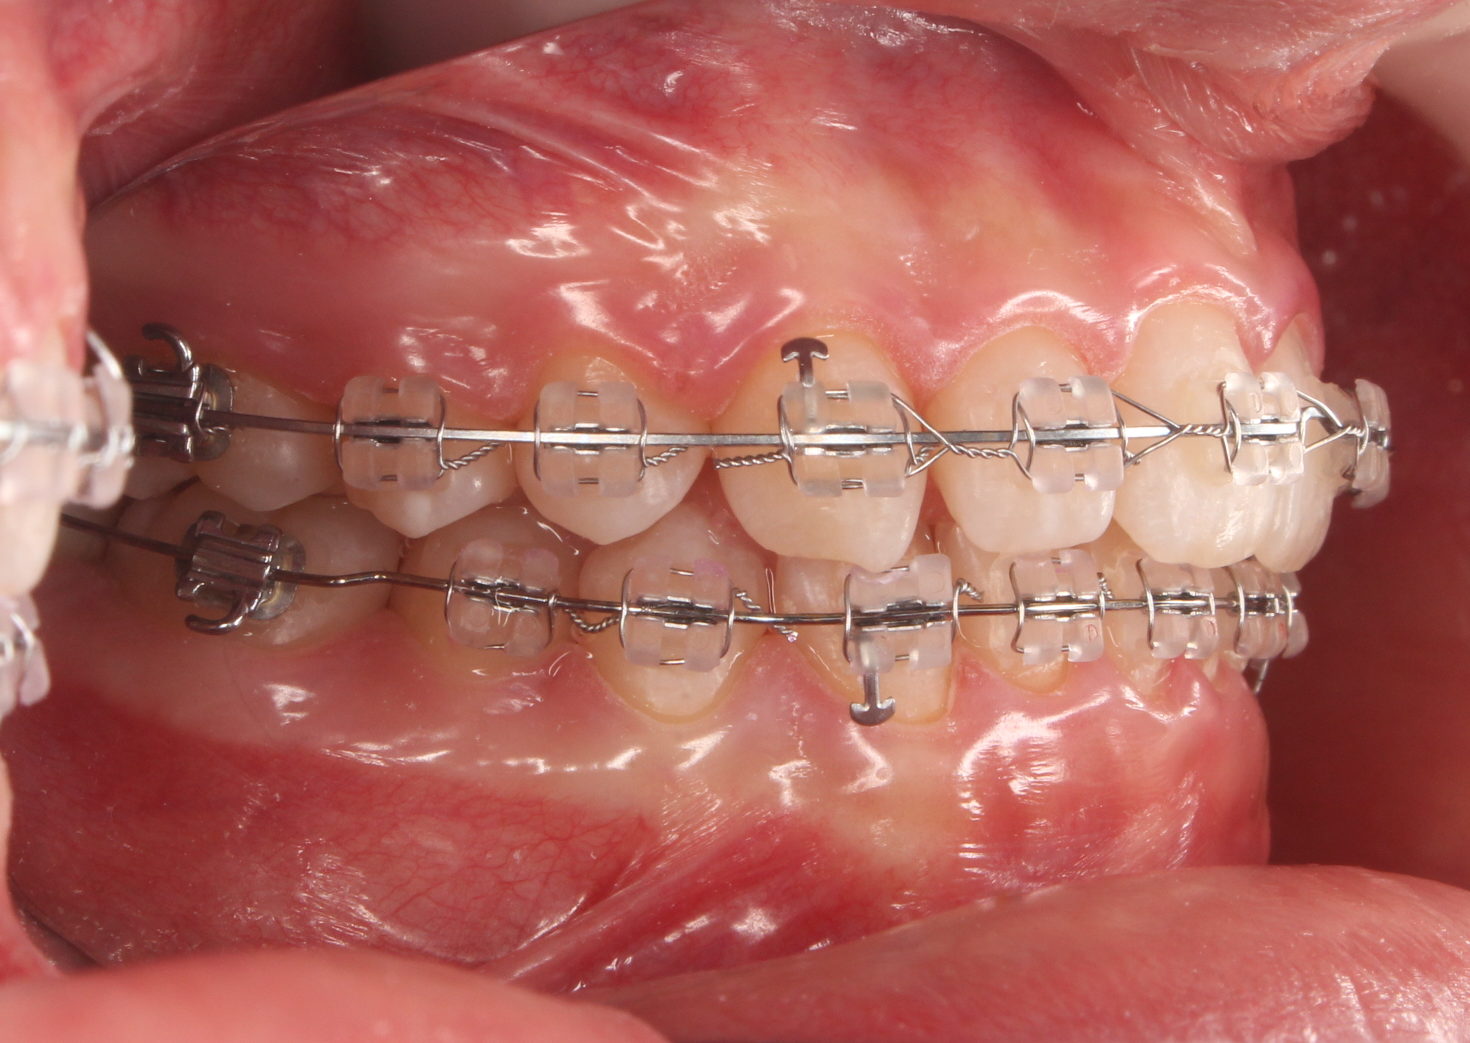

ワイヤー矯正 だいぶ良くなりました(^-^)

こんにちは。 南館歯科クリニックの院長の木村です。 成人矯正を行っている症例についてご紹介します。 歯並びと顎の歪みが気になるとのことで来院された方です。 診断後 治療とその限界についてよく相談し 外…